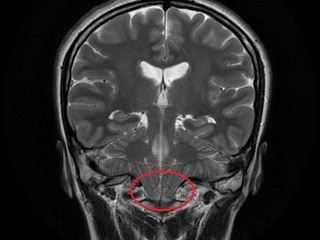

Рис. 1. Данные МРТ и КТ до и после операции. а — МРТ головного мозга до операции: видна клиновидная деформация миндаликов мозжечка и их дислокация в большое затылочное отверстие ниже уровня дужки С1 позвонка; б, в — КТ головного мозга спустя 12 ч после операции: видно, что новое положение костного лоскута (указан желтой стрелкой) позволяет увеличить диаметр большого затылочного отверстия и объем задней черепной ямки; г — МРТ спустя 3 мес после операции: миндалики мозжечка занимают нормальное положение, виден просвет большой затылочной цистерны, нет признаков псевдоменингоцеле.

Послеоперационное течение. Течение послеоперационного периода было гладким, осложнений не отмечено. Компьютерная томография спустя 12 ч после операции подтвердила удовлетворительное положение костного лоскута (см. рис. 1, б, в. и рис. 3). Пациентка выписана домой спустя 36 ч после операции и вернулась к занятиям в школе через неделю после нее. При контрольном осмотре спустя 3 мес после операции она отметила полный регресс головной боли, боли в шейно-затылочной области, приступы судорог после операции также не повторялись. МРТ головного мозга через 3 мес после операции (см. рис. 1, г) выявила нормальное положение миндаликов мозжечка, появление просвета большой затылочной цистерны, признаков псевдоменингоцеле не было.